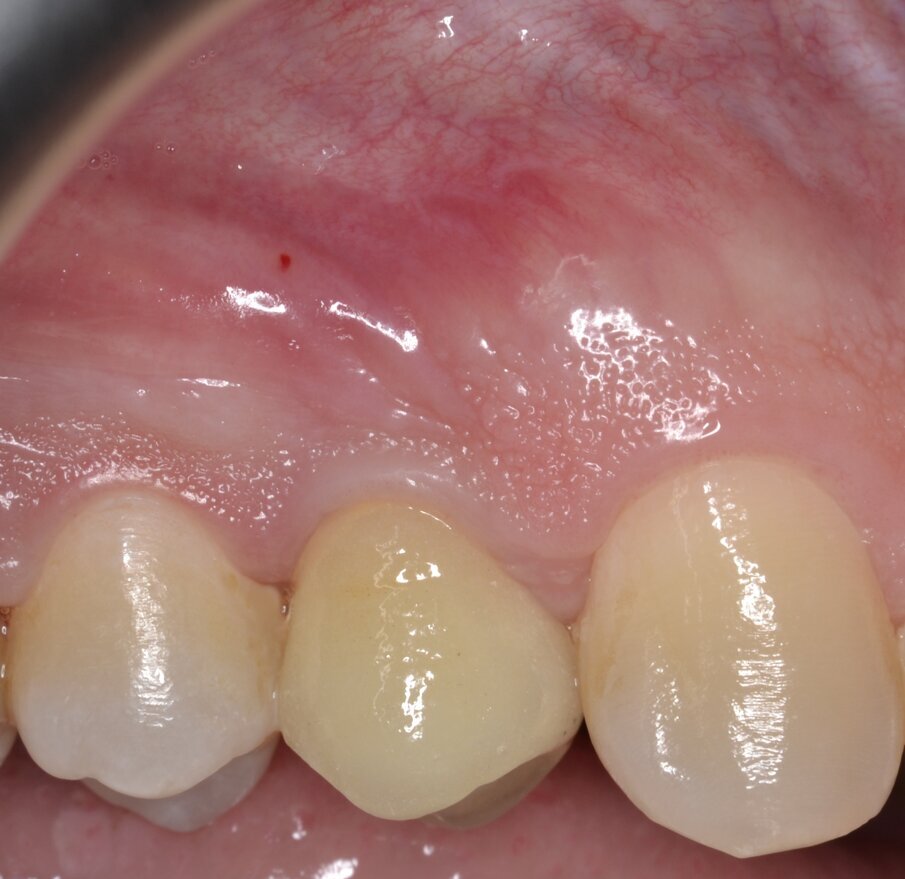

Dopo aver opportunamente preparato un abutment definitivo che sia idoneo per altezza e forma del segmento transmucoso, si procede alla cementazione di una corona protesica definitiva in zirconia stratificata. Le immagini del follow-up a 12 mesi (Figg. 23-25) e il contestuale controllo radiografico endorale (Fig. 26) indicano un’ottima risposta dei peri-implantari tessuti duri e molli.

Fig. 23 - Corona protesica definitiva in zirconia stratificata (visione buccale).

Fig. 24 - Corona protesica definitiva in zirconia stratificata (visione occlusale).

Fig. 25 - Corona protesica definitiva in zirconia stratificata (visione orale).